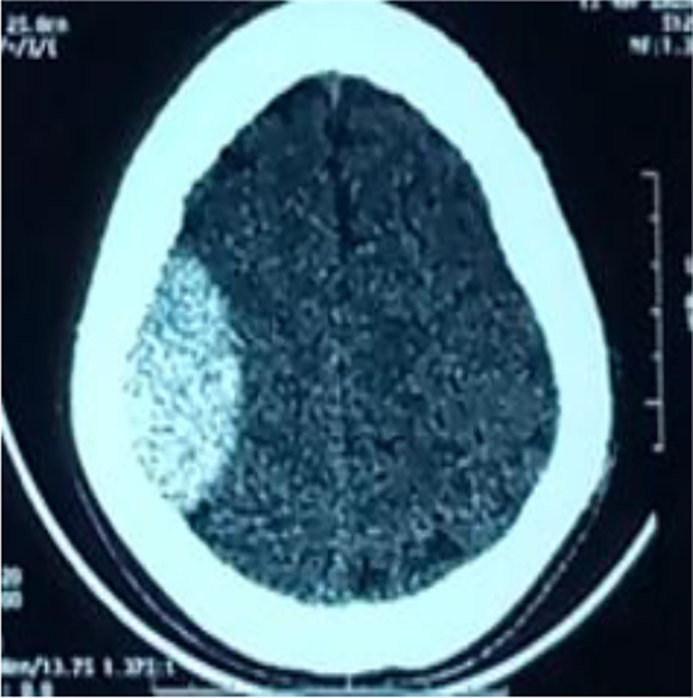

He underwent emergency surgery, and surgical evacuation of the hematoma after a right parietal flap was made. The bone was hemorrhagic, with no fractures or signs of soft tissue trauma. The patient was transfused with packed red blood cells and 5 platelet concentrates. The postoperative course was marked by neurological deterioration and the appearance of right anisocoria, prompting an emergency CT scan, which revealed an intraparenchymal hematoma associated with a 10 mm thick subdural fronto-parieto-occipital haematoma and diffuse cerebral oedema (Fig. 3), necessitating emergency surgery. The patient was transferred to the intensive care unit and died of multi-visceral failure. This work has been reported in line with the Surgical Case Report (SCARE) criteria [4].

Fig. 3. Post-operative CT scan showing an intra-parenchymal haematoma with a subdural haematoma lamina, diffuse cerebral oedema, and meningeal hemorrhage.